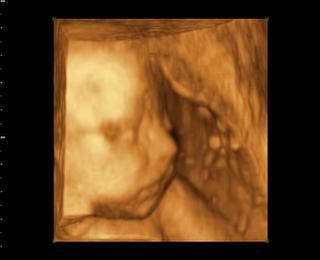

@lucy56 morfoligicky utz je zameraný na hodnotenie správnosti vývoja jednotlivých orgánov plodu a zároveň sa odmeraním určitých parametrov hodnotí aj správnosť rastu dieťaťa. nebudes tak dobre vidiet dietatko ako na 3D. 3D utz :Moderný 3D ultrazvuk umožňuje vidieť pohyby Vášho bábätka, ako na filmovom plátne. Pohľad do tváre pôsobí na budúcu mamičku ukľudňujúco. Prepočítajme spolu prstíky a presvedčme sa, že je všetko v poriadku.Celé vyšetrenie je možné uchovávať na DVD nosiči.Najvhodnejší je záznam v 22-26. týždni tehotenstva.